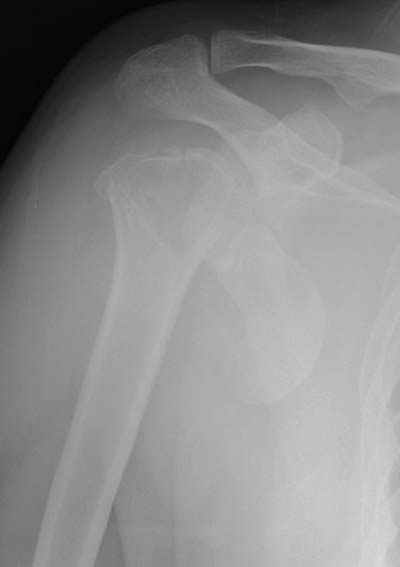

Здесь случай перелома-вывиха плеча, больному 56 лет, после "дважды" закрытой неудачной репозиции, опять же ургентно взяли в операционную, после полного общего обезболивания попытались сделать репозицию, и фиксацию провели спицами.

Больной находился в повязке, примерно напоминяющей косыночную, рекомендованы движения в локтевом суставе и маятниковые движения в плече, спицы удалены в три недели (были случаи миграции)

Больной амбулаторный, предупрежден на случай осложнения АВН головки.